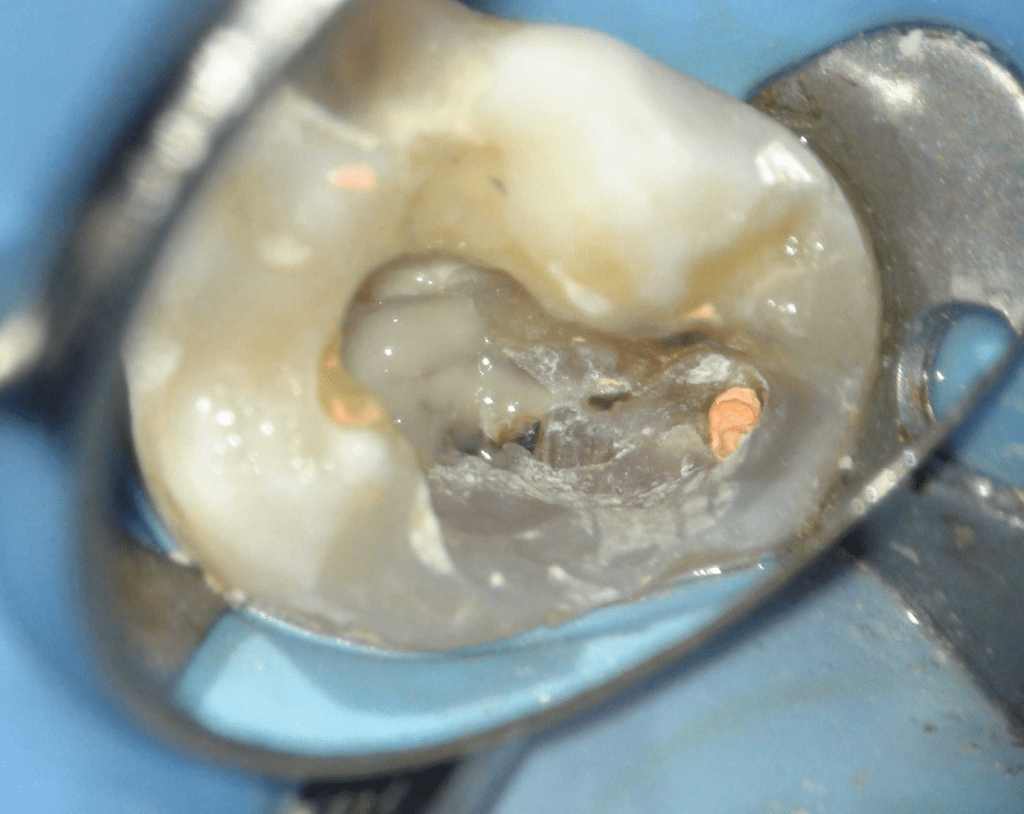

Pulpotomía biodentine + reco preendio